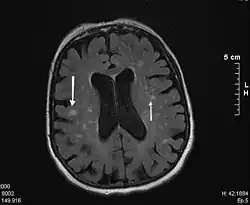

En la Tomografía Computarizada, la leucoaraiosis se observa como regiones con menor densidad, mas oscuras que las circundantes, es decir áreas hipodensas, en Imagen por Resonancia Magnética se define como lesiones con mayor intensidad de señal es decir áreas hiperintensas, por presentar un aspecto más brillante que las zonas aledañas. Estas imágenes pueden verse en las regiones próximas a los ventrículos cerebrales, corona radiata y centro semioval.[9] Se han utilizado escalas cualitativas como la de Fazekas para determinar el grado de las lesiones: